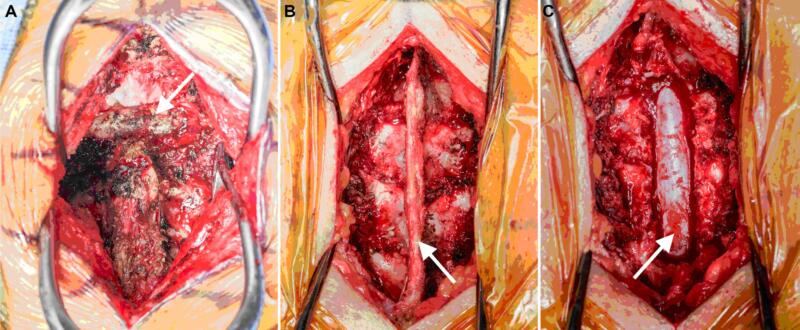

BN điều trị nội khoa thất bại hoặc có dấu hiệu chèn ép thần kinh, có thể cần phải chỉ định phẫu thuật (hình 1). Phẫu thuật nhằm cắt bản sống để giải ép các cấu trúc thần kinh, loại bỏ mô nhiễm khuẩn, và lây mô nuôi cấy định danh chủng gây bệnh. Nếu cột sống mất vững, có thể cần phải tiến hành làm cứng cột sống bằng xương ghép và đôi khi có bắt phương tiện kim loại. Xương ghép tự thân (autograft) được ưa thích hơn xương ghép đồng loại (allograft) vì giảm nguy cơ nhiễm trùng so với xương ghép đồng loại. Mặc dù một số phẫu thuật viên không dùng kim loại để làm cứng cột sống, nhưng nếu cần dùng thì nên sử dụng titanium hơn là thép không gỉ (stainless steel) vì titanium giảm nguy cơ nhiễm trùng (khả năng bám dính và tạo màng sinh học của vi khuẩn lên titanium kém hơn lên thép không gỉ). Trong một số trường hợp, để giảm nguy cơ nhiễm trùng, phẫu thuật làm cứng (fusion) cột sống có thể được thực hiện sau khi giải ép một thời gian, tức là mổ giải ép trước, điều trị kháng sinh, sau khi nhiễm trùng đã ổn định và được kiểm soát thì mổ làm cứng cột sống; hoặc có phẫu thuật viên mổ tháo phương tiện sau khi chụp phim kiểm tra thấy đã liền xương tốt.

Viêm xương đốt sống có thể xảy ra và thường liên quan nhiều đốt sống và đĩa đệm, tình trạng nhiễm khuẩn lan qua nhiều đĩa đệm đến thân đốt sống (hình 2). Xử trí ban đầu bao gồm sinh thiết để nuôi cấy xác định chủng vi khuẩn, cấy máu, và kháng sinh theo kinh nghiệm trong khi chờ kết quả nuôi cấy. Những BN này thường có tình trạng nhiễm khuẩn xương đáng kể, và cần được phẫu thuật để loại bỏ tổ chức nhiễm khuẩn. Cột sống mất vững có thể là hậu quả của tình trạng nhiễm khuẩn hoặc do phẫu thuật loại bỏ tổ chức nhiễm khuẩn. Do tình trạng nhiễm khuẩn đa số xảy ra ở thân đốt sống và đĩa đệm nên đường mổ theo lối trước hoặc lối bên được các phẫu thuật viên ưa thích hơn, vì dễ tiếp cận và làm sạch tổ chức nhiễm trùng, kiến thiết lại cấu trúc cột sống. Đường mổ lối sau hiếm khi được sử dụng trừ khi nhiễm trùng liên quan đến bản sống hoặc cuống cung đốt sống hoặc nếu cột sống quá mất vững và cần làm cứng thêm ở phía sau.

Hình 17. Phẫu trường mổ cột sống: A. Đường mổ ở cột sống cổ lối sau, tách cơ, bộc lộ các mỏm gai đốt sống cổ ở đường giữa, mũi tên chỉ nền của xương chẩm. B. Đường mổ ở đốt sống ngực lối sau, tách cơ, bộc lộ bản sống, mỏm gai và dây chằng gian gai (mũi tên). C. Cắt bỏ mỏm gai, bản sống để giải ép tủy sống (mũi tên).